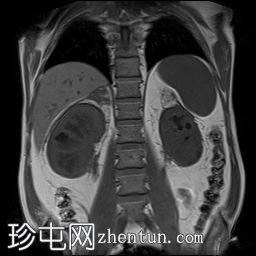

冠状位

T2加权像

双肾包膜及肾周软组织增厚,呈光滑对称性,后侧及右侧更为明显。增厚延伸至肾门及近端输尿管周围,导致轻度双侧肾积水。左侧肾周可见局灶性纤维化带,可能为局灶性纤维化。整体影像学表现提示肾周纤维化或浸润性病变。

左肾相对较小,皮质轻度变薄,下极可见两个边界不清、T2信号低、无限制性病变。这些病变可能与纤维化灶或肿瘤(例如乳头状肾细胞癌和淋巴瘤)相符。右肾实质厚度正常,未见局灶性病变。

双侧肾上腺肿大,伴软组织增厚,但未见明显肿块。

Erdheim-Chester病(ECD)是一种罕见的非朗格汉斯细胞组织细胞增生症,其特征是多个器官出现黄色肉芽肿性浸润。典型的肾脏受累表现为双侧对称性肾周软组织增厚,常累及肾门和近端输尿管周围。肾上腺周围浸润也较为常见。

左肾的病变可能是与该病相关的纤维化肾实质内病变,也可能是肿瘤性病变,例如肾乳头状细胞癌或淋巴瘤。需要进一步评估。